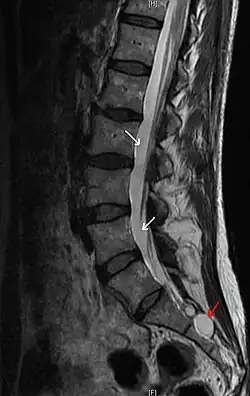

Die mit dem roten Pfeil markierte Arachnoidalzyste ist isointens zur Rückenmarksflüssigkeit (weiße Pfeile). Sagittale T2-gewichtete Kernspintomographie der Wirbelsäule

Isointensität (von griechisch ίσος = gleich und lateinisch intensus = gespannt) bedeutet "gleiche Signalstärke". Radiologen verwenden den Begriff bei der Befundung von kernspintomographischen Aufnahmen, wenn zwei Strukturen im Bildeindruck gleich hell sind. Man vermeidet die umgangssprachlichen Wörter "hell" bzw. "dunkel" bei der Beurteilung von medizinischem Bildmaterial, weil diese Qualitäten bei der Monitorbefundung variiert werden.

Aus der Isointensität zu bekannten anatomischen Strukturen lassen sich Aussagen über das fragliche Gewebe ableiten. Beispielsweise sind die meisten Zysten in den kernspintomographischen Routinesequenzen zum Inhalt der Harnblase isointens.